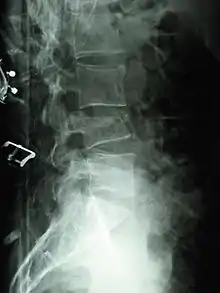

Una fractura por compresión[1][2] es el colapso de una vértebra. Puede deberse a un traumatismo o al debilitamiento de la vértebra (comparar con una fractura por estallido). Este debilitamiento se observa en pacientes con osteoporosis u osteogénesis imperfecta, lesiones líticas de tumores primarios o metastásicos, o infección. En pacientes sanos, se observa con mayor frecuencia en personas que sufren choques verticales extremos, como la expulsión de un asiento de eyección. En las vistas laterales de las radiografías simples, las fracturas por compresión de la columna aparecen característicamente como deformidades en cuña, con mayor pérdida de altura en la parte anterior y posterior y pedículos intactos en la vista anteroposterior.

Las fracturas por compresión generalmente se diagnostican en las radiografías de la columna vertebral, donde una vértebra con forma de cuña puede ser visible o puede haber pérdida de altura de la vértebra. Además, la medición de la densidad ósea se puede realizar para evaluar la osteoporosis. Cuando se sospecha que un tumor es la causa subyacente o si la fractura fue causada por un traumatismo grave, se pueden realizar tomografías axiales computarizadas o resonancias magnéticas.